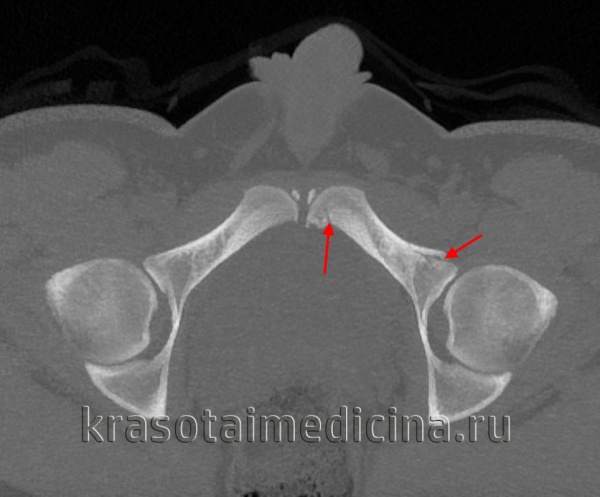

3. КТ при изолированной травме таза:

• Улучшенная визуализация переломов таза с отсутствием смещения

• Позволяет отличить изолированные переломы от травм тазового кольца